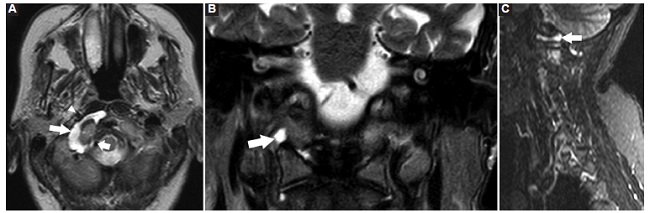

Presentamos dos casos en los que se realizó resonancia magnética (RM) de columna cervical, sin gadolinio. El primero, una mujer de 66 años sin antecedentes relevantes ni enfermedades concomitantes, que consultó por dolor cervical irradiado a ambos miembros superiores. Se realizó radiografía (Rx) de columna cervical, en la que se encontraron signos incipientes de espondiloartrosis. La RM mostró signos de espondiloartrosis y DAAO derecho (Fig. 1).

La presencia de DAAO es un hallazgo inusual, bien valorado en la RM con cortes axiales ponderados en T2/STIR con supresión grasa, objetivándose como una colección semilunar hiperintensa, adoptando una morfología en C, rodeando al cóndilo occipital, entre la arteria carótida interna ventralmente y la arteria vertebral dorsalmente.